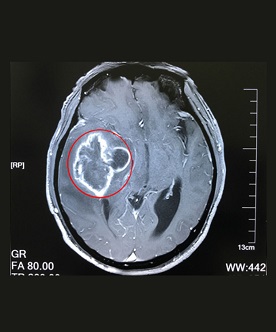

在確診腦膠質(zhì)瘤時(shí),一定要做的必然是檢查。那,腦膠質(zhì)瘤需要做哪些檢查?上海藍(lán)十字腦科醫(yī)院專家解析:膠質(zhì)瘤(gliomas)是發(fā)生...【詳細(xì)】